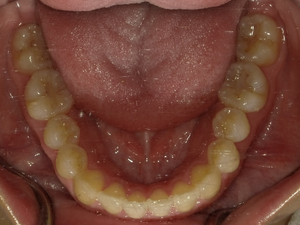

●ご相談内容:歯がガタガタしてる●矯正の種類:マウスピース型矯正「インビザライン」●治療期間:26週間●治療費用:66万円(税込)